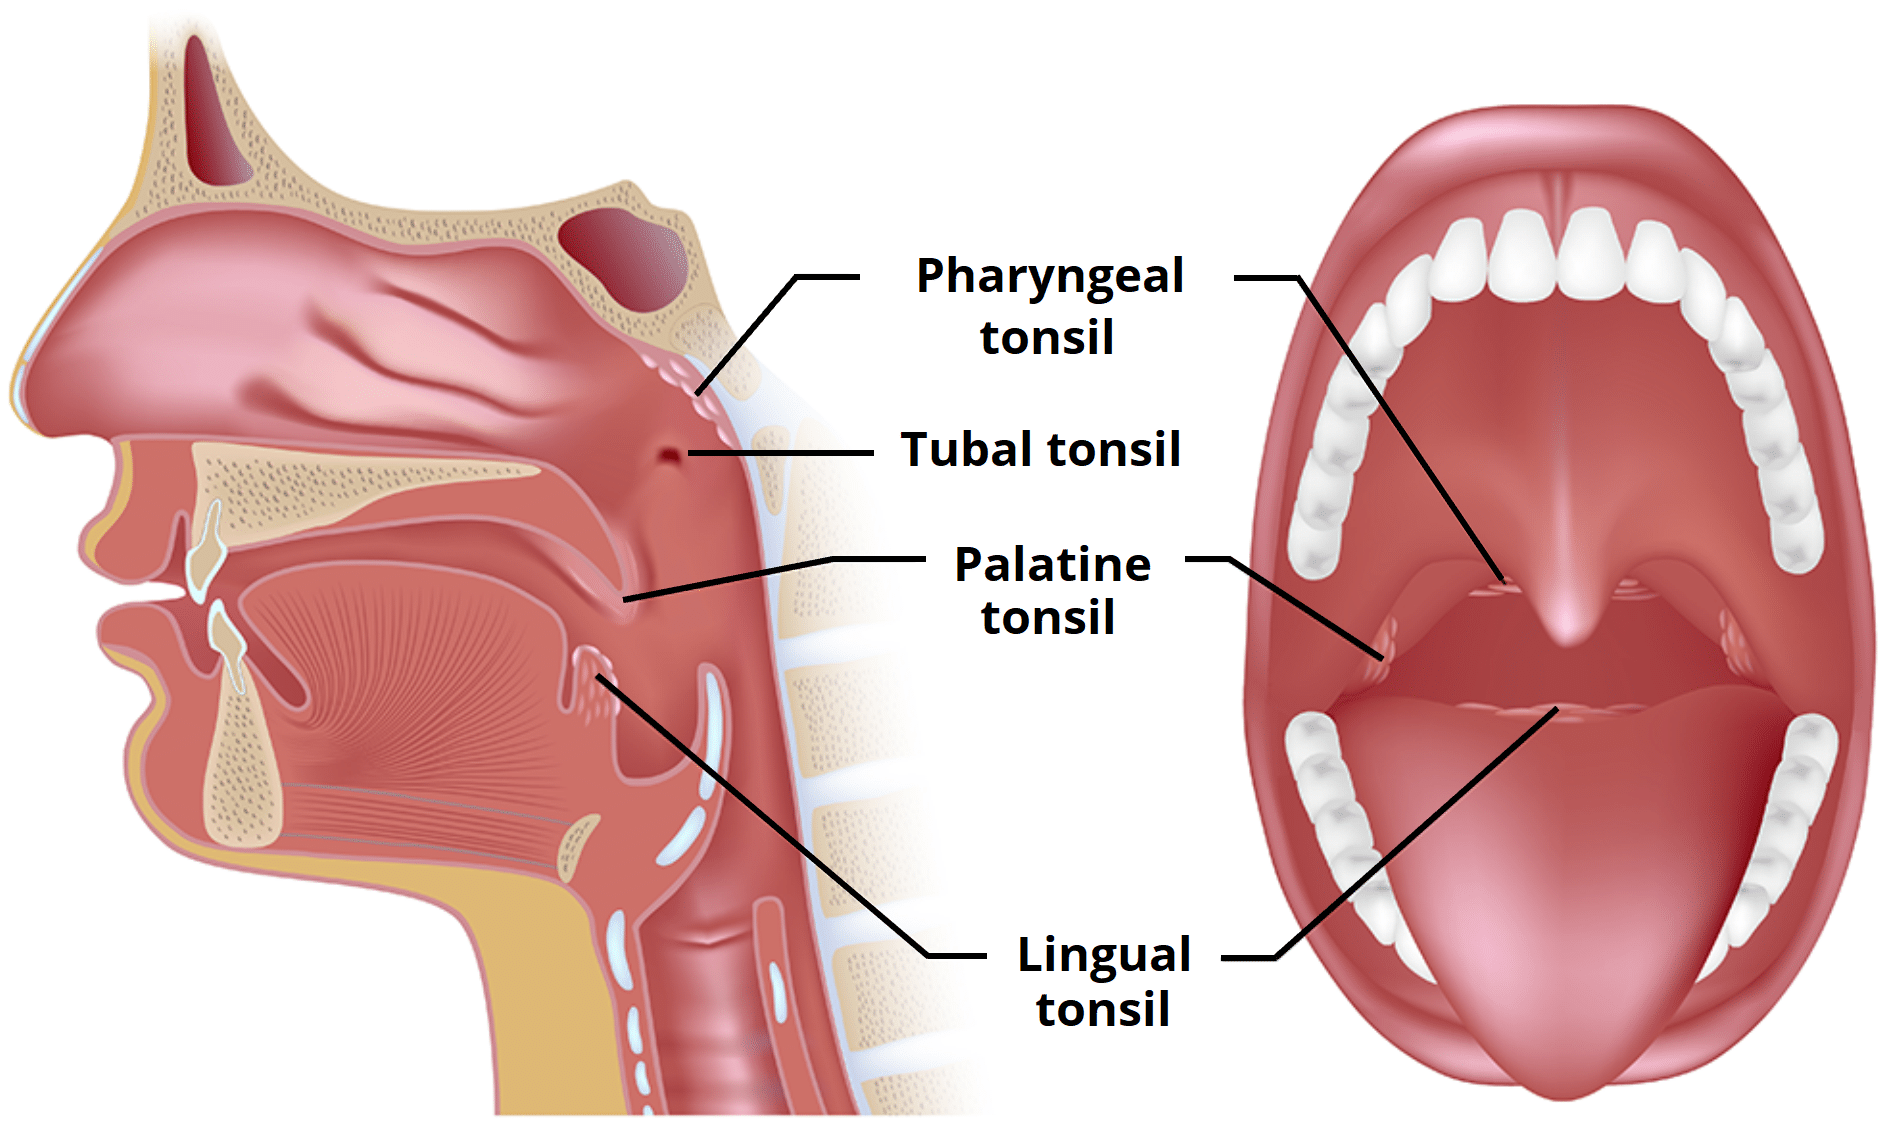

Tonsil

Waldeyer’s tonsillar ring

Nasopharynx

- Pharyngeal tonsil

Oropharynx

- Palatoglossal fold(arch)

- Palatine tonsil

- Palatopharyngeal fold(arch)